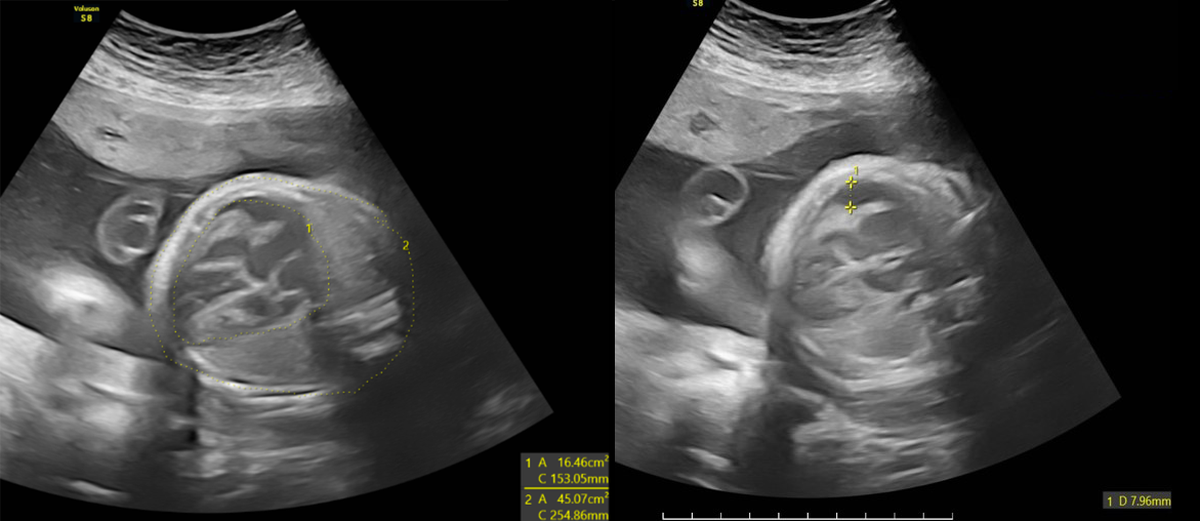

- Giãn não thất hai bên và giãn hố sau: Hình ảnh giãn não thất hai bên rõ rệt, kèm giãn hố sau, là dấu hiệu tổn thương não nghiêm trọng, có nguy cơ gây chậm phát triển trí tuệ, động kinh hoặc các biến chứng thần kinh sau sinh.

Các bất thường ở thai nhi được phát hiện trên hình ảnh siêu âm

Những hình ảnh siêu âm này phản ánh mức độ nghiêm trọng của tình trạng nhiễm trùng thai nhi. Ngay sau khi thực hiện siêu âm, BSCKI. Trần Thế Quỳnh - Chuyên khoa Chẩn đoán hình ảnh, Phòng khám Đa khoa MEDLATEC Thanh Xuân - người trực tiếp thực hiện siêu âm trường hợp này đã thông báo chi tiết cho thai phụ về các bất thường, giải thích ý nghĩa của từng hình ảnh. Đây là những dấu hiệu tiên lượng nặng có thể gây nhiều biến chứng cho thai như bại não, điếc bẩm sinh... Kết quả hội chẩn cùng các bác sĩ tuyến trên, chị P. có chỉ định đình chỉ thai kỳ do tiên lượng xấu.